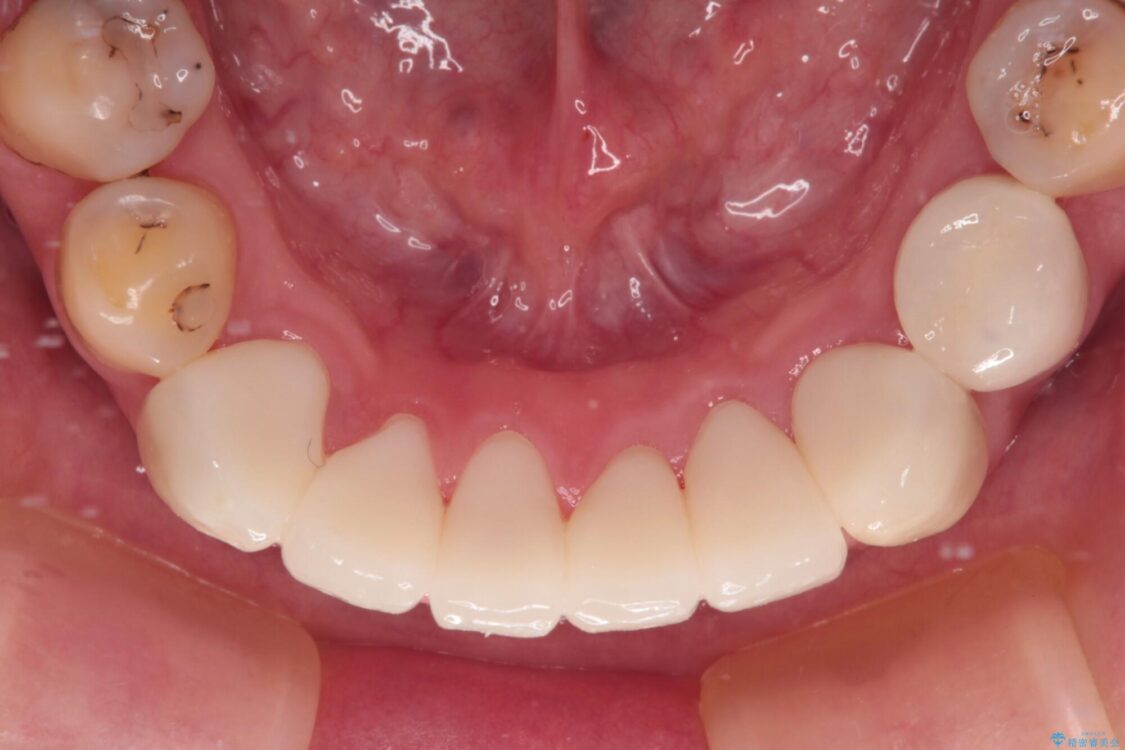

治療途中

• むし歯だらけの前歯をオールセラミッククラウンできれいに 治療途中画像

治療後

• むし歯だらけの前歯をオールセラミッククラウンできれいに 治療後画像